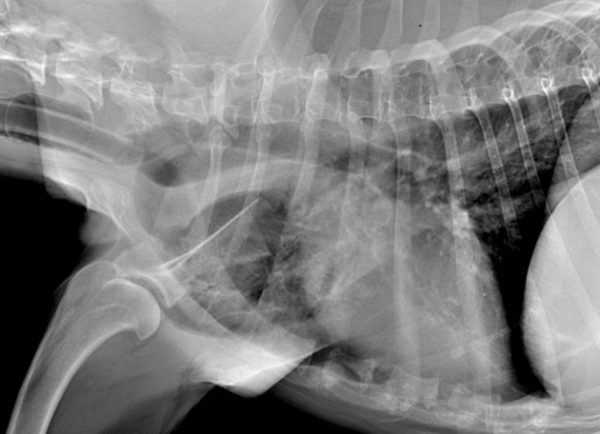

Un examen radiographique est réalisé sur animal vigile. Le coude gauche présente une dégradation arthrosique déjà avancée que l’on retrouve également sur le coude droit. Une déformation des tissus mous est visible en regard de la portion caudale de la scapula. L’articulation scapulo-humérale ne présente pas d’anomalie, seule la scapula présente des modifications de son architecture sur sa face interne avec une corticale effacée, une association d’ostéolyse et d’ostéoproduction (fig. 2 et 3).

Une hypothèse tumorale étant envisagée, un bilan d’extension pulmonaire est réalisé (une radiographie de chaque profil + une radiographie de face) mais ne met aucune métastase en évidence.